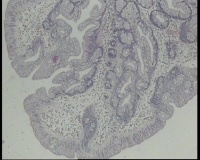

镜下见息肉表面腺体乳头状增生,间质水肿,血管充血,少量浆细胞、淋巴细胞浸润,部分腺体扩张,腺腔不规则,粘液细胞增多,上皮细胞无明显异型改变,请老师看看这个报绒毛管状腺瘤吗?(跟以前看的不一样)

传统锯齿状腺瘤。

绒毛状腺瘤。